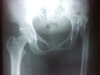

고관절 화농성 관절염이 영아기에 왔으나, 당시에는 열이 나고 울고 보채는 등의 비특이적 증상만 보였으므로 잘 몰랐거나 수술적 치료 시기가 늦어지거나 해서 대퇴골두가 아예 녹아버릴 수 있습니다. 환자가 자라면서 생각보다 아프지는 않지만, 한쪽 다리가 짧고 절뚝거리게 되므로 보기에 좋지 않습니다.

대퇴골두가 완전히 녹지 않고 일부만 손상된 경우, 조기에 수술을 했기에 그나마 대퇴골두가 남아 있는 것으로, 이차적으로 퇴행성 관절염이 오기 쉽습니다. 특히 결핵균의 경우 진행이 느려 일찍 대퇴골두가 일부분만 녹은 뒤 치료되는 사례도 빈번합니다. 이런 경우 다리 길이는 짧지 않은데, 젊을 때는 통증이 없거나 운동 후에만 통증이 있는 정도로 그치나 나이가 들어 퇴행성 관절염으로 진행되면 늘 통증을 느끼게 됩니다.

X-ray : 화농성 관절염(Pyogenic arthritis)의 후유증